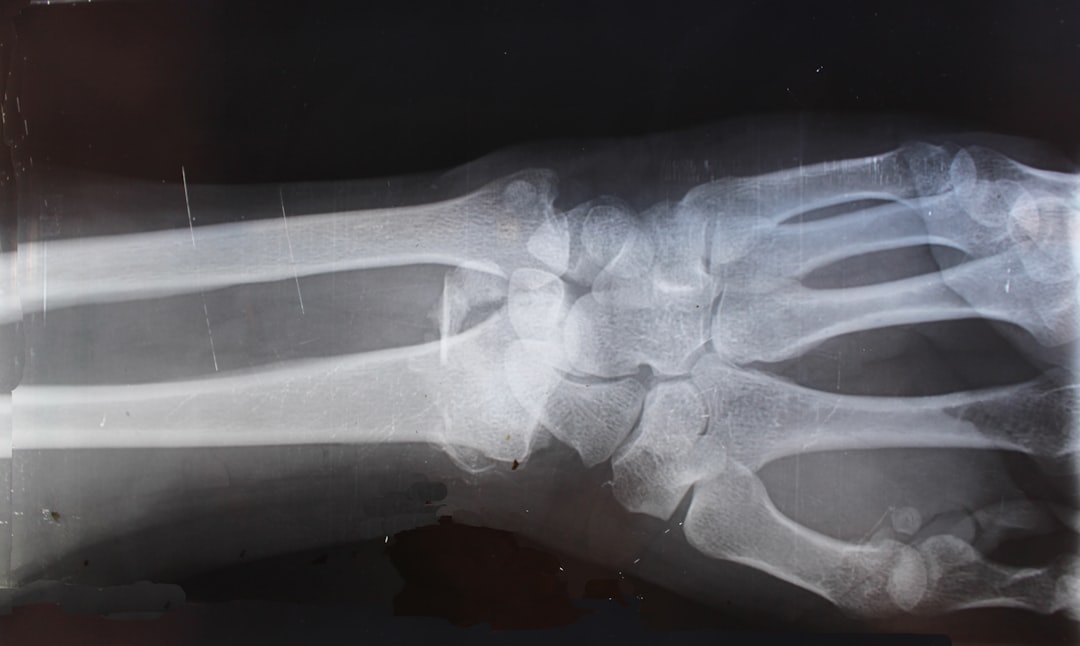

If you’re ready to explore how reconstructive surgery can change your life, now is the time to act. The longer you wait, the more you miss out on living fully. By scheduling a consultation, you’ll take the first step toward restoring your function and confidence. We take care of both hand fractures and wrist fractures, and can get live X-rays in the office to better understand and plan further care.